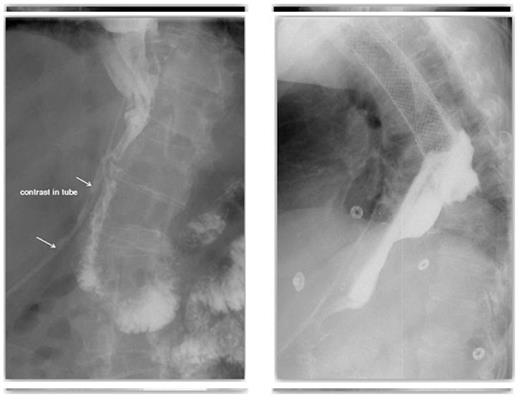

On post-operative day 16 a late pyloroplasty leak was diagnosed on contrast swallow (Figure 3). This presented as a persistent leak of bile stained discharge from the abdominal drain. After failure of initial conservative treatment an attempt to control the leak was made.

The defect at the pyloroplasty suture line was now visible endoscopically and a covered pyloric stent was located appropriately across the defect. Due to proximal stent migration this was unsuccessful in controlling the leak (Figure 4). The patient still had a controlled fistula from the pyloroplasty suture line.

A late pyloroplasty leak diagnosed on contrast swallow & A contrast swallow demonstrating proximal stent migration and evidence of on-going leak